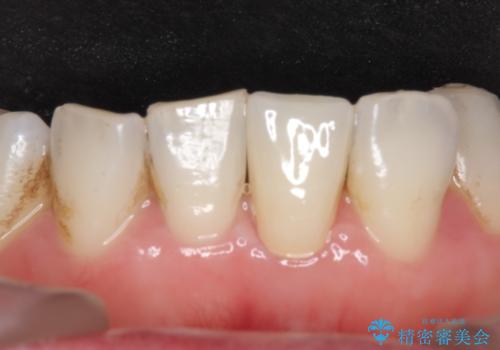

- 下顎前歯が茶色いのが気になるのでセラミックで治療したいといらっしゃった方の症例です。

再根管治療後、オールセラミッククラウン(スペシャル)による補綴を行いました。

前歯の補綴ではオールセラミッククラウンを希望される患者様が多いですが、オールセラミッククラウンの中でも、エコノミー、スタンダード、スペシャル、エクセレントとランクがあります。

その中でも特に審美性が高いのがスペシャル、エクセレントです。スペシャル、エクセレントは口腔内写真をもとに熟練の技工士が、患者様の口腔内に合わせたオーダーメイドのクラウンを製作致します。